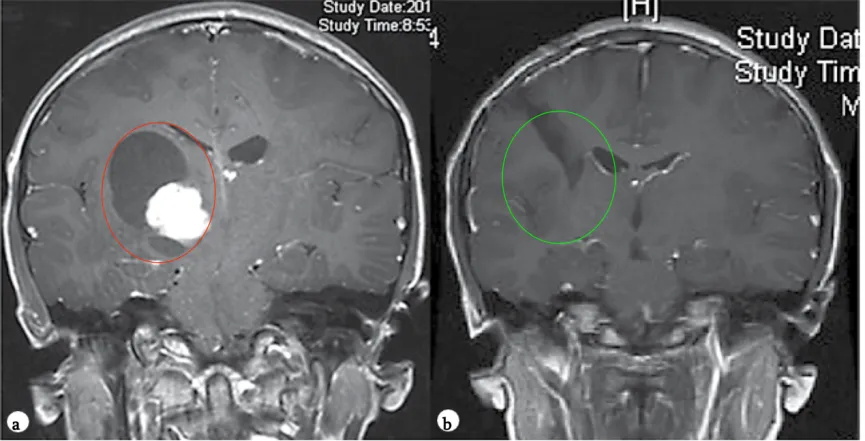

2、9岁女孩——丘脑毛细胞星形细胞瘤

病情回顾:头痛、四肢无力、频繁呕吐,检查结果显示:右侧丘脑占位。

治疗难点:丘脑较大肿瘤,皮质脊髓束(负责人体肢体运动的神经传导束)受压,脑室扩大,手术风险大。

手术结果:James T.Rutka教授顺利全切肿瘤,预后无并发症、没有复发,对孩子的成长发育和智力没有造成任何影响。